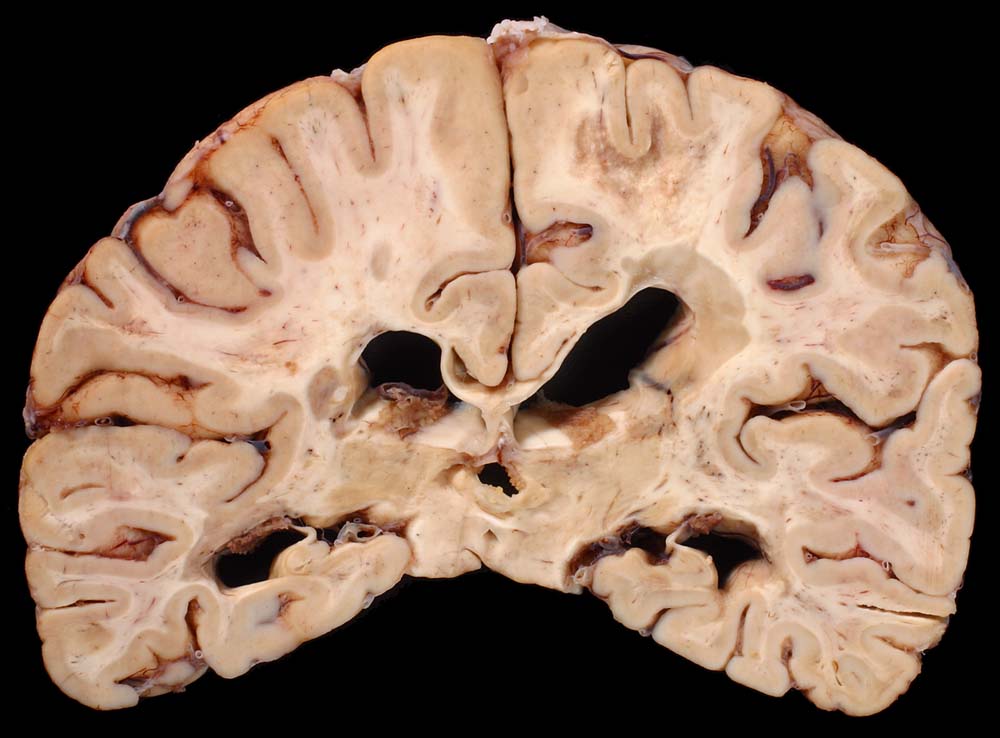

Entmarkungsherde bei Multipler Sklerose

Periventrikulär betonte fleckförmige Grauverfärbung des Marklagers ( Entmarkungsareale).

Chronische und aktive Entmarkungsareale in der weissen Substanz (beidseits, periventrikulär betont).

Diagnose einer multiplen Sklerose vor 12 Jahren. Paraparese der Beine. Neurogene Blasenentleerungsstörung. Seit einem Jahr deutliche neurologische Verschlechterung.